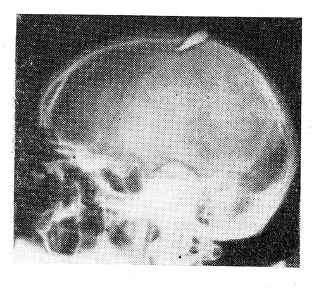

В январе 1959 г. при надевании противогаза отметил резкие боли в области рубца на левой половине головы. Обратился к врачу, который назначил ему рентгенографию черепа. На рентгенограммах черепа, неожиданно для больного и врача, был обнаружен (рис. 1 и 2) отломившийся кончик ножа размером 4,5х1,2 см, проникающий через обе пластинки левой теменной кости в полость черепа на глубину около 1 см. Инородное тело расположено в среднем отделе теменной кости на расстоянии около 4 см от стреловидного шва.

Рис. 1. На рентгенограмме черепа видно инородное тело в левой теменной области.